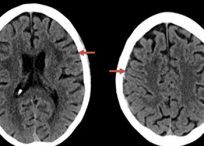

- Brisman MH, Bederson JB, Sen C, Germano IM, Moore F, Post KD: Intracerebral Hemorrhage Occurring Remote from the Craniotomy Site. Neurosurgery 39: 1114-1122, 1996